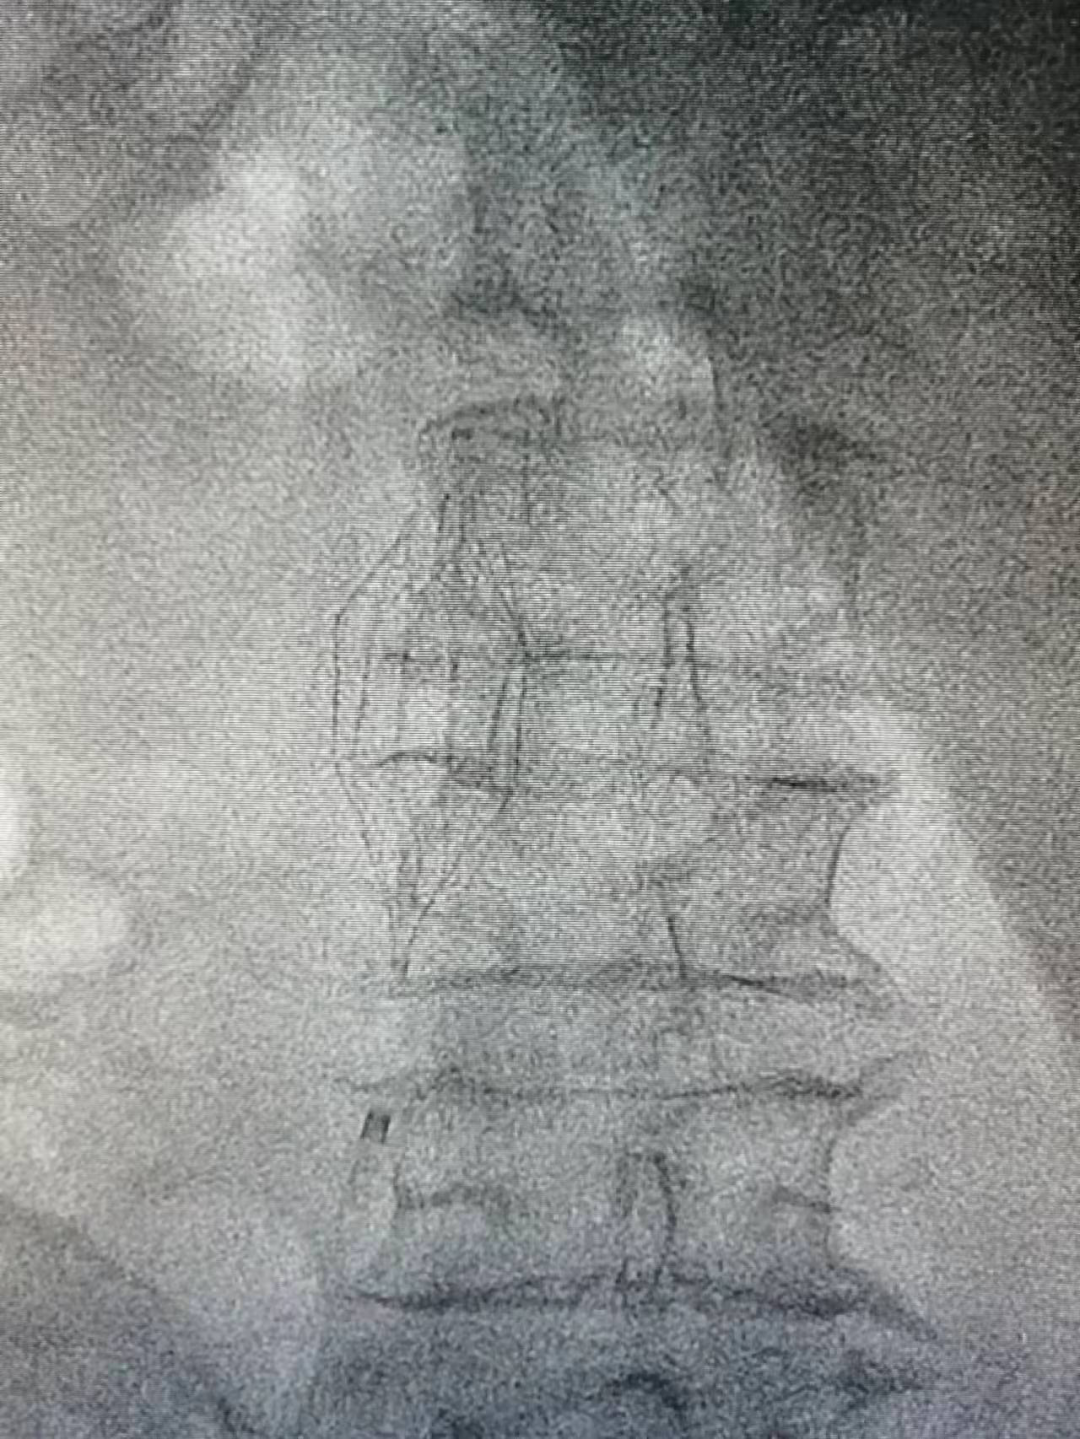

经过与患者及家属沟通并征得同意后,由北京专家陈晓东、神经外科主任田德洲科指导,神经外科副主任董永军、张晨主治医师、高磊磊医师行下腔静脉滤器植入术,取右侧腹股沟下方局麻,穿刺右侧股静脉。定位后释放滤器,滤器贴壁满意。手术历时半个小时,术后继续抗凝治疗2周后行下静脉滤器取出术,患者安返病房。